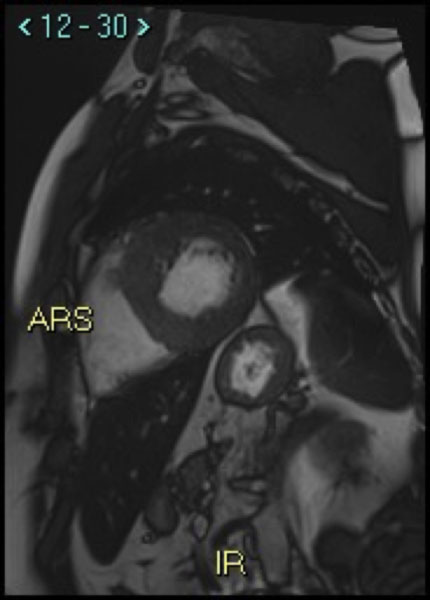

La sindrome di Noonan

“Trattiamo le aritmie cardiache dallo studio dei geni all’ablazione transcatetere“